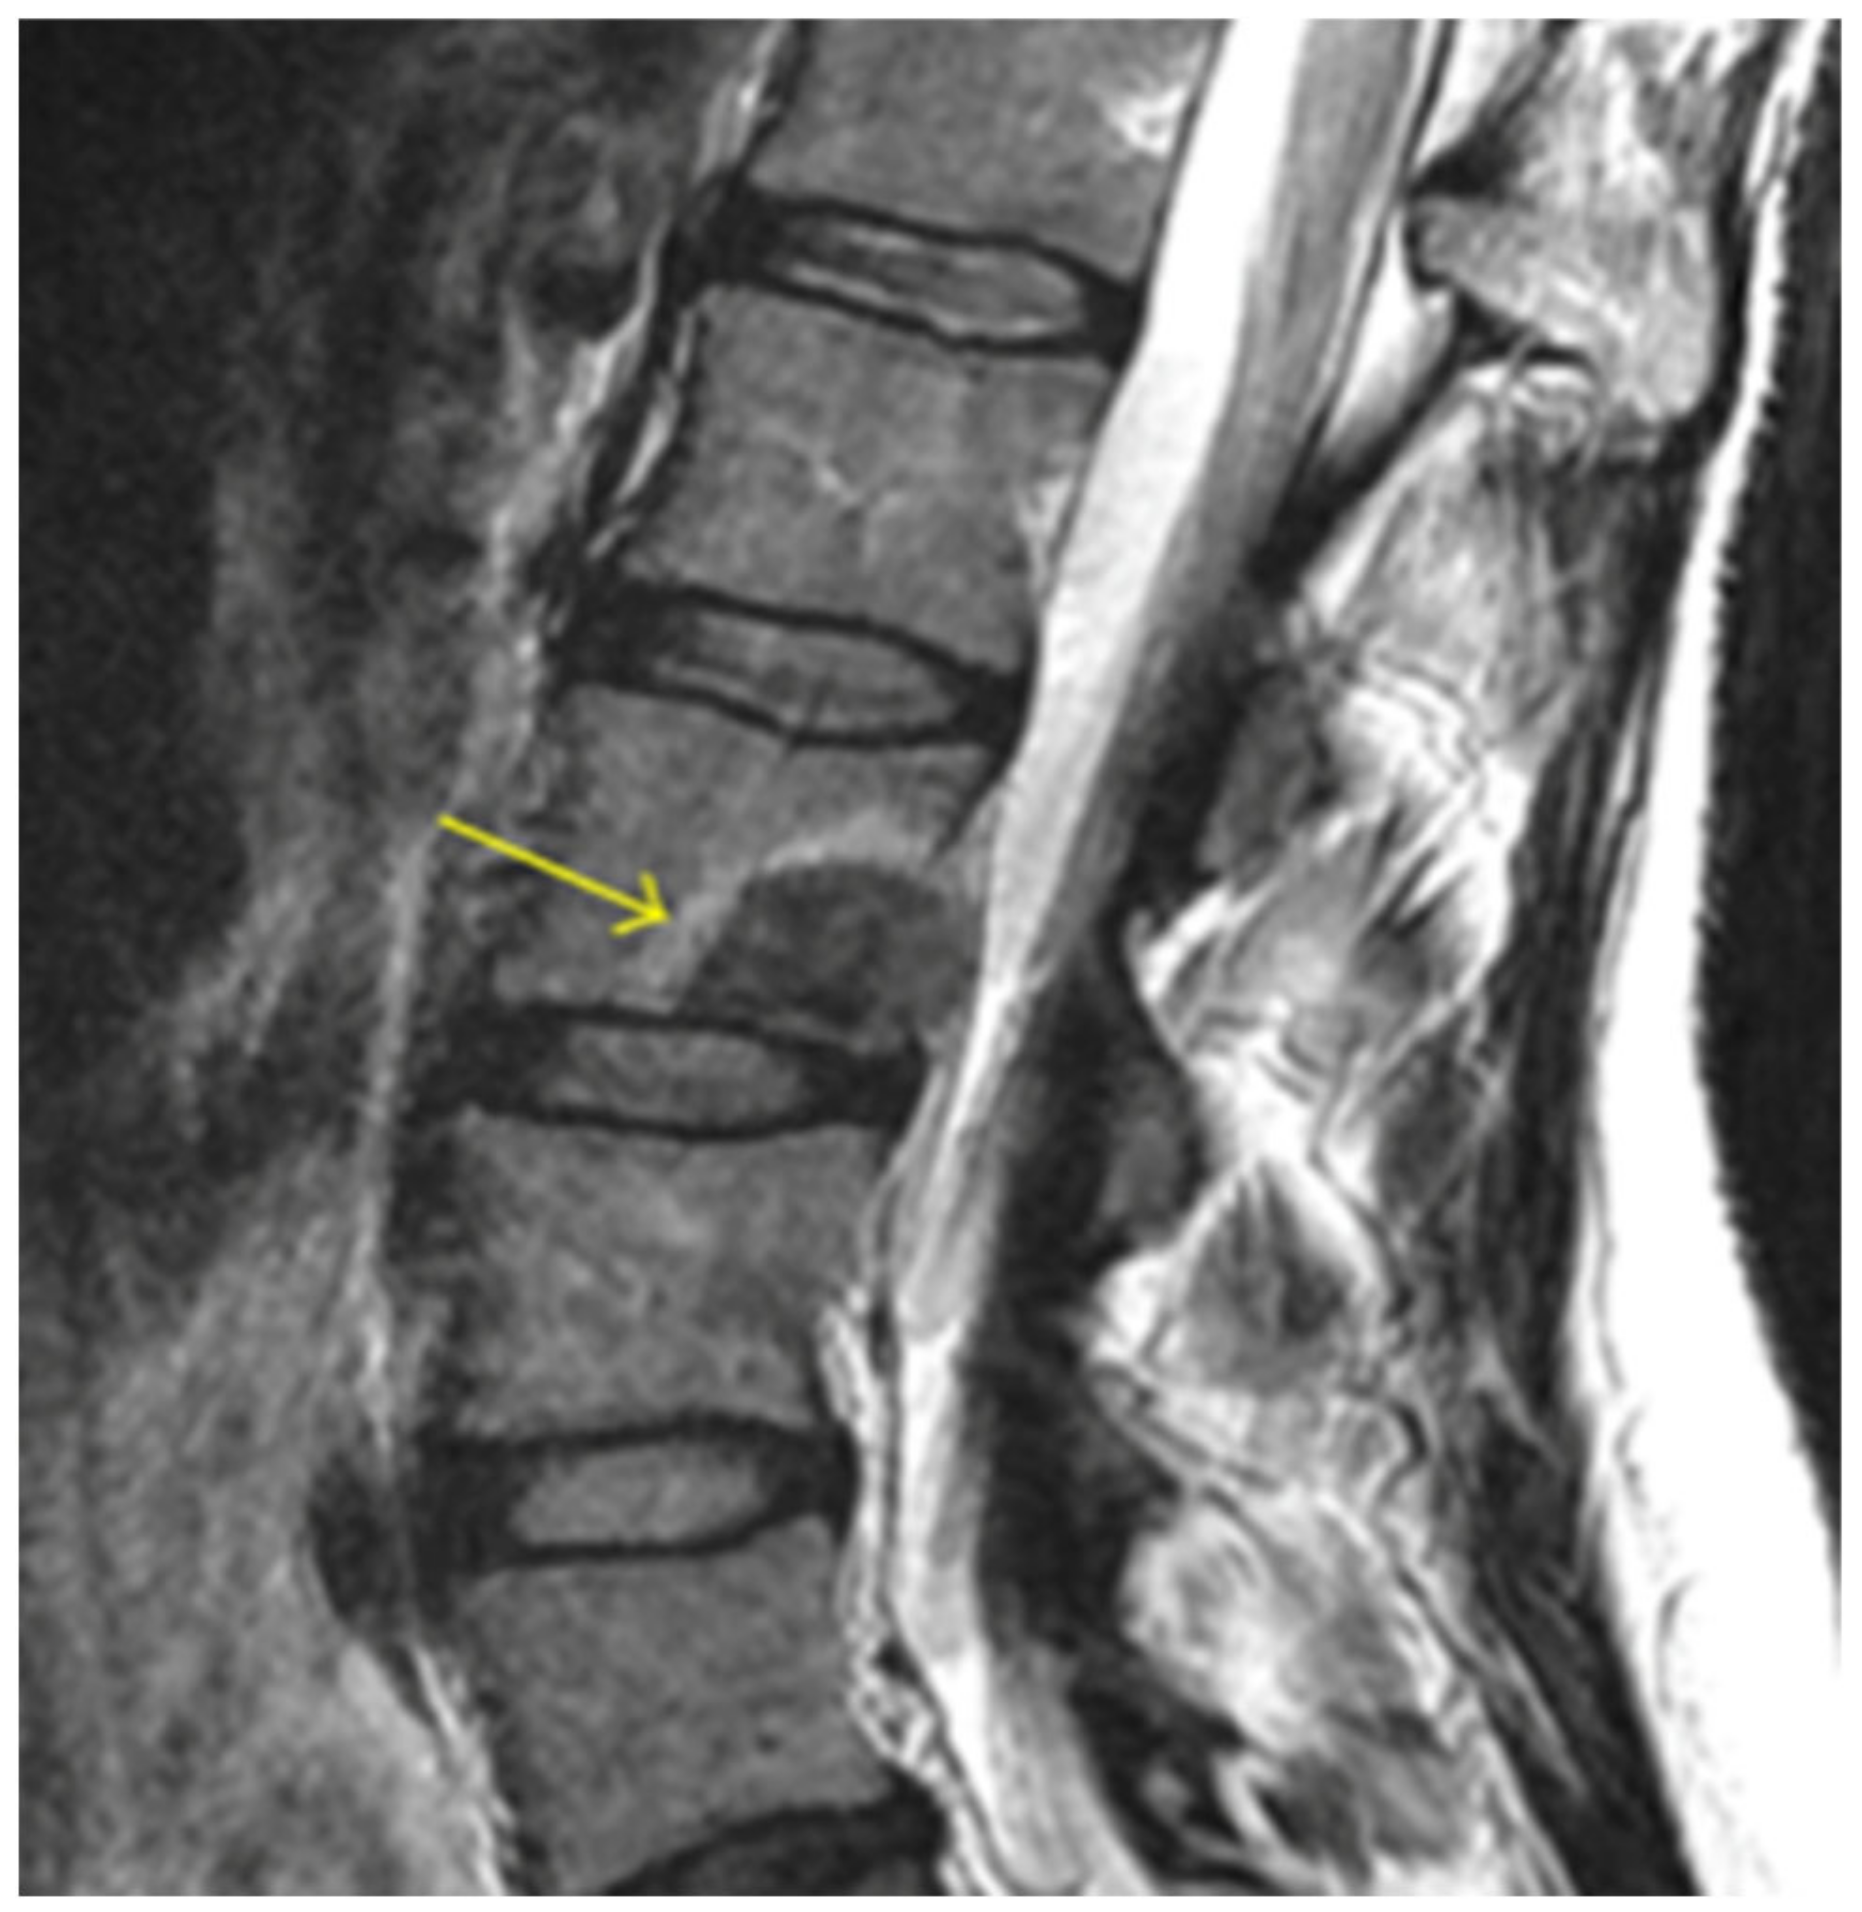

Vertebral tumors are benign or malignant growths that involve the vertebral body of the spinal column (Figure 2). Nearly all malignancies are the result of metastasis (97%) rather than primary solid vertebral body tumors. The spine is affected in 30–70% of metastatic diseases with the vertebral bodies, especially throughout the thoracic and lumbar spine, cited as the third most common site for osseous metastasis [55,56]. This association is largely a function of the rich vascular and lymphatic connections to common sites of cancerous tissue throughout the thorax and pelvis [57]. The spine is involved in 65–75% of breast and prostate malignancies, 30–65% of lung cancers, more than 40% of metastatic thyroid cancers, and about 30% of renal cell carcinomas [58,59,60,61]. Although much less common, primary spinal tumors include multiple myeloma, osteosarcoma, hemangioma, osteoid osteoma, aneurysmal bone cyst, chondrosarcoma, etc. [62].

Figure 2.

Lumbar spine magnetic resonance image (MRI) with an arrow pointing at the posterior–inferior edge of the vertebral body, highlighting a vertebral body tumor.